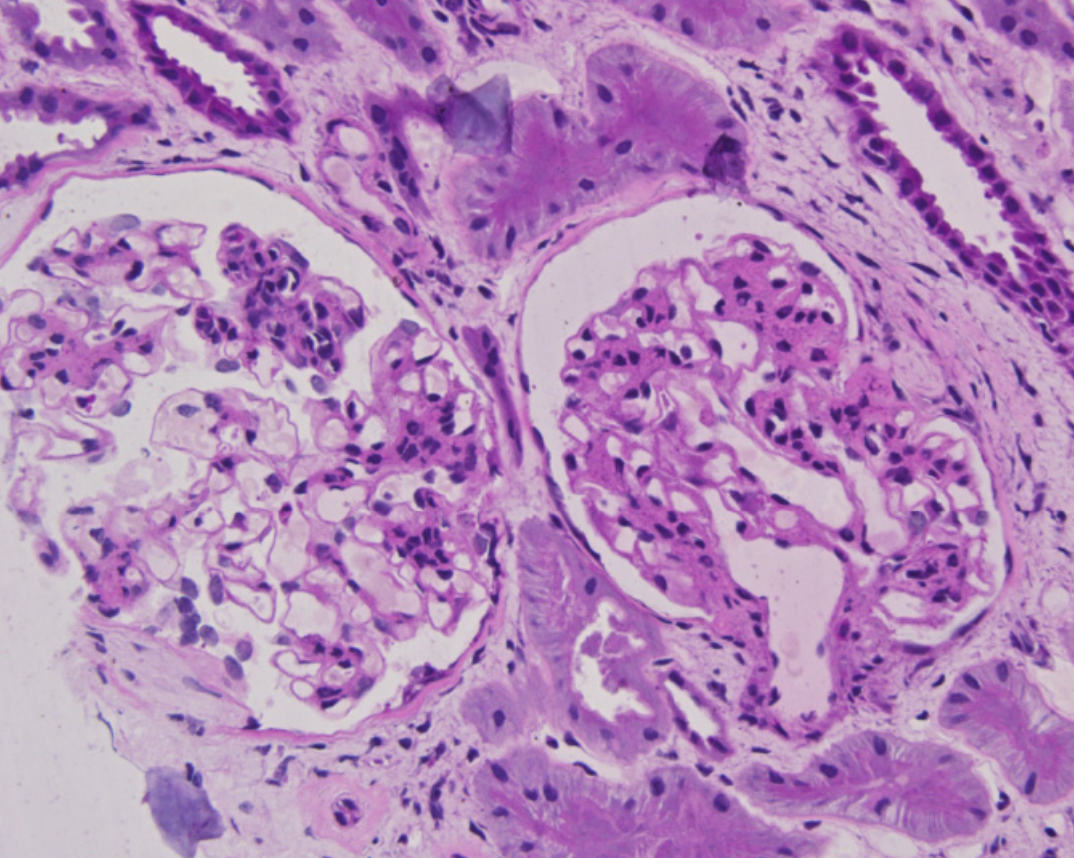

Appréciée sur la coloration PAS. Est cotée M1 si plus de la moitié du glomérule comporte plus de 3 cellules dans l’aire mésangiale. Ne pas compter les aires mésangiales en proximité immédiate du pédoncule vasculaire.